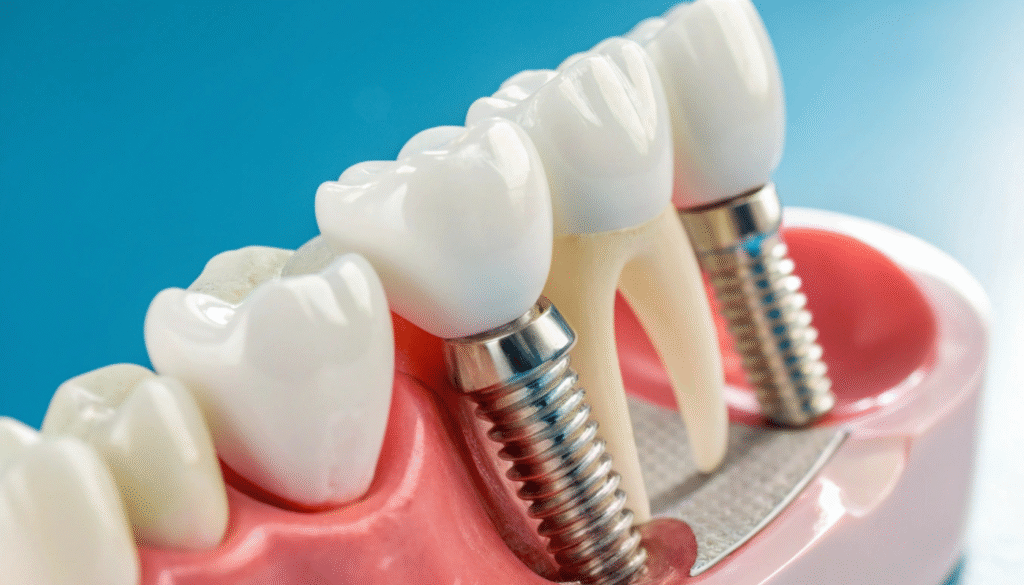

Dental Implants

Replaced teeth cannot be removed, as they are fixed in the mouth, and FPDs are brushed and cleaned just like natural teeth. So, Their neighboring teeth give them support. Also, to support an FPD, dentists must make the teeth smaller so the prosthesis fits. As a disadvantage, you have to intentionally reduce healthy natural teeth. Additionally, depending on patient preferences and replacement sites, these can be full metal, metal-ceramic, or zirconia.